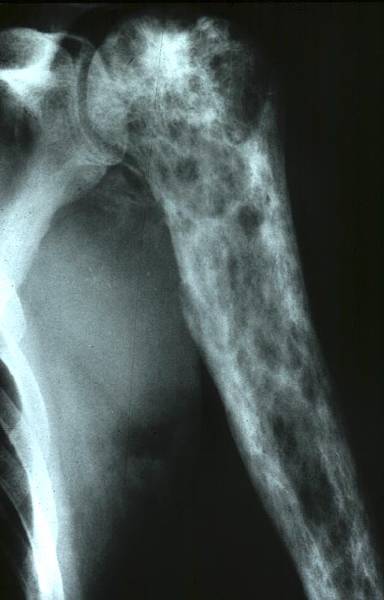

Quel diagnostic pour cette tumeur osseuse?

A

Chondrome de la diaphyse fémorale car matrice cartilagineuse

Tumeur osseuse visiblement maligne: quel est le diagnostic probable?

Lésion épiphysaire à matrice cartilagineuse (pop corn) d’allure maligne = Chondrosarcome de l’humérus